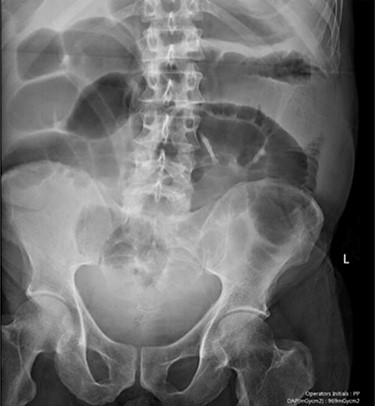

Blood tests on admission were unremarkable. Each admission, the patient’s plain abdominal films showed dilated large bowel loops consistent with sigmoid volvulus (Fig. 1). A subsequent computed tomography (CT) of the abdomen and pelvis with intravenous contrast revealed dilated large bowel and was reported as sigmoid volvulus with no evidence of perforation (Fig. 2). Caecal volvulus was not appreciated on this scan.

Case one: plain abdominal film showing dilated large bowel and the ‘coffee bean’ sign associated with sigmoid volvulus.